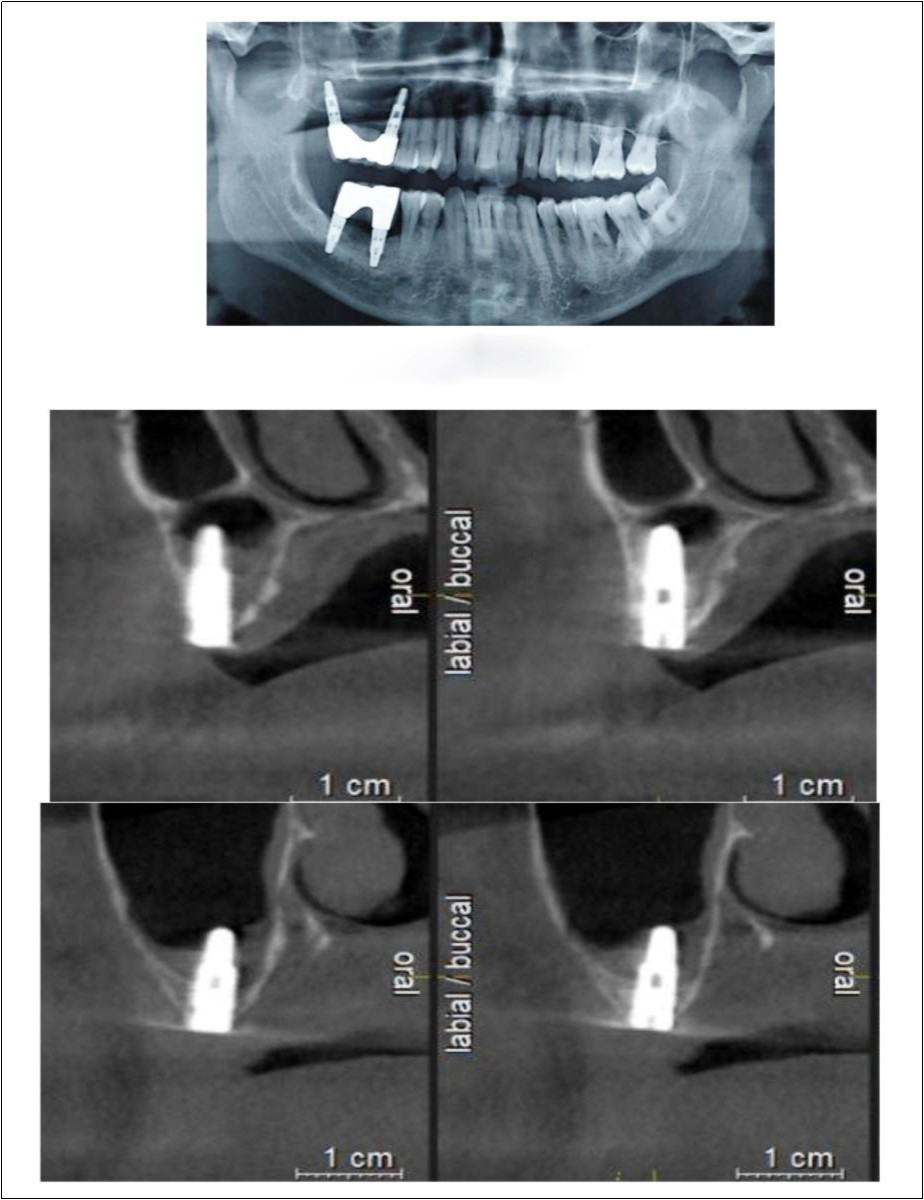

Case Report 2

A 45 year old patient with a residual bone height of 6.6 mm in 17 region underwent procedure of indirect sinus elevation using sinus osteotomy in relation to 17 region. Synthetic graft material was dispensed through the crestal osteotomy site to maintain the elevated sinus membrane followed by placement of a dental implant measuring 5 mm x 10 mm under local anesthesia and strict aseptic protocols. The implant was allowed to osseo-integrate for a period of six months during which the patient was followed periodically and was assessed for peri-implantitis, crestal bone loss and mobility. At the end of 6 months, a CBCT scan was advised to evaluate the increase in bone height which was 12mm. (Figure 3, Figure 4)

Figure 3.Pre-operative Orthopantomograph and cross section of CBCT showing residual alveolar bone height

Figure 4.Post-operative Orthopantomograph and cross section of CBCT showing residual alveolar bone height